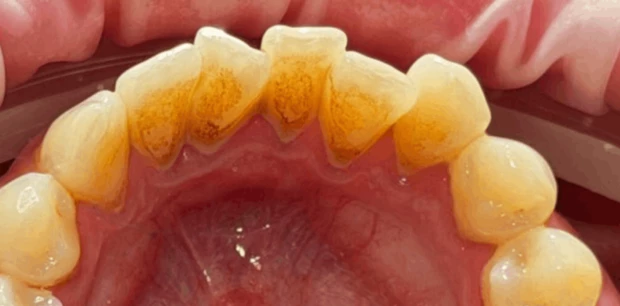

Профгигиена

Профессиональная гигиена полости рта

Выполнено удаление зубного налёта и камня: восстановлен естественный цвет эмали, улучшено состояние дёсен и профилактика воспалений.